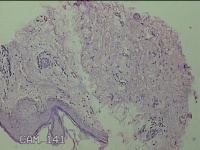

左大腿皮下结节

性别

女

年龄

30岁

临床诊断

皮下结节

一般病史

发现左大腿皮下结节1年余。

标本名称

大体所见

灰白粉红色组织1.7x0.8x0.3cm一个,表面带梭形皮肤 1.3x0.7cm,皮下见结节1.7x0.7cm一个,切开结节呈实性,切面灰白灰白粉红色,质中。

图4